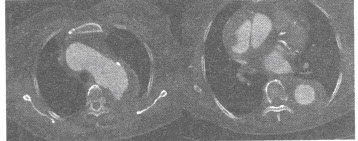

患者,男,41岁,刺激性咳嗽3个月余,低热1周,近3天咳痰带血丝。胸部CT如图,最可能的诊断为()

A:淋巴瘤肺浸润

B:炎性病变

C:中央型肺癌并左肺下叶阻塞性炎症

D:周围型肺癌

E:细支气管肺泡癌并淋巴结转移